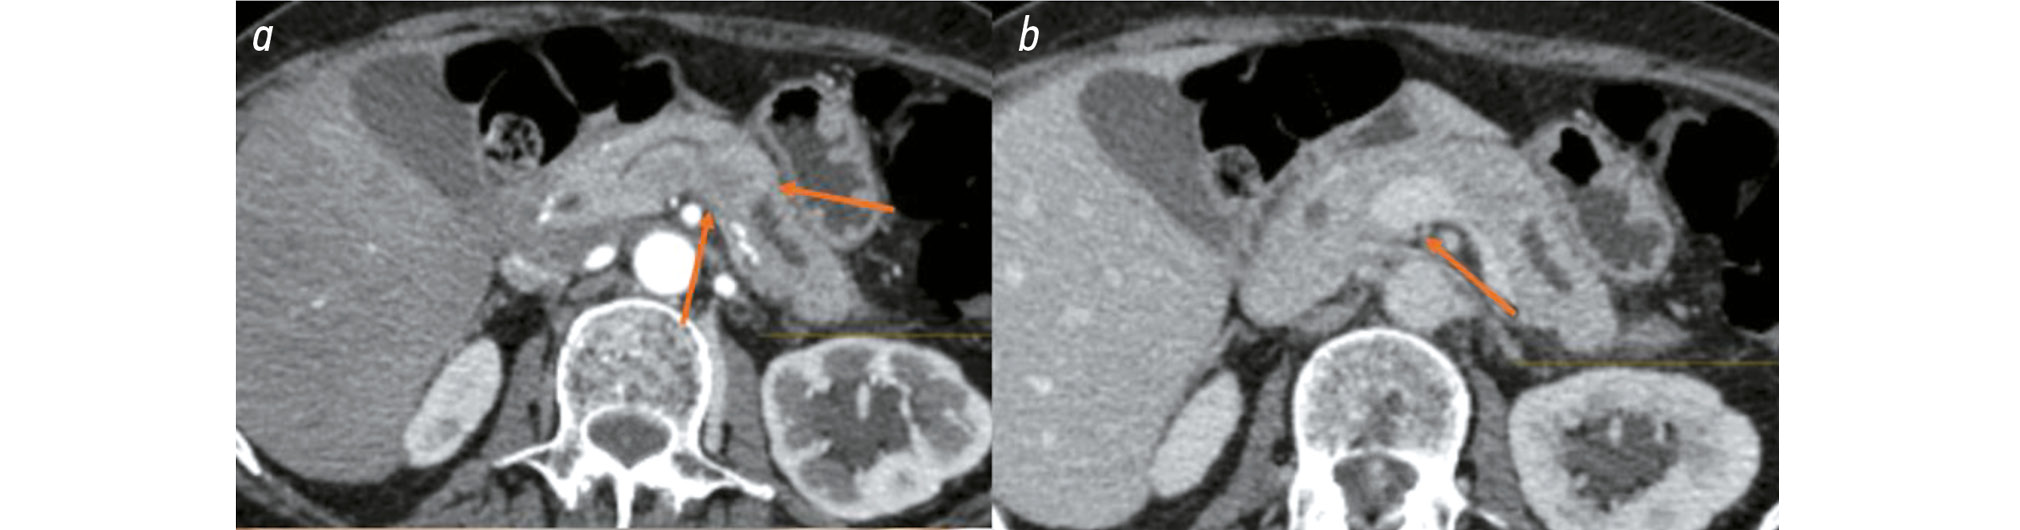

Pancreatic NETs exhibit the greatest contrast enhancement during the early arterial phase (25–35 s), rather than the late arterial phase (35–45 s), which is typically used for pancreatic imaging. This distinction is important because small tumors may be missed during the late arterial phase when the lesion becomes isodense with the surrounding pancreatic tissue [12]. Fig. 1 illustrates characteristic imaging features of pancreatic NETs. Abdominal CT with intravenous contrast revealed a hypervascular lesion in the head of the pancreas, measuring 13 × 9 mm, located near the pancreatic duct and common bile duct, without clear signs of duct compression on CT. The tumor demonstrated marked contrast enhancement during the early arterial phase (10 s) but was poorly visualized in the subsequent contrast phases.

Fig. 1. Abdominal computed tomography with intravenous contrast: a, a hypervascular lesion near the common bile duct during the arterial phase (10th second); b, venous phase image.